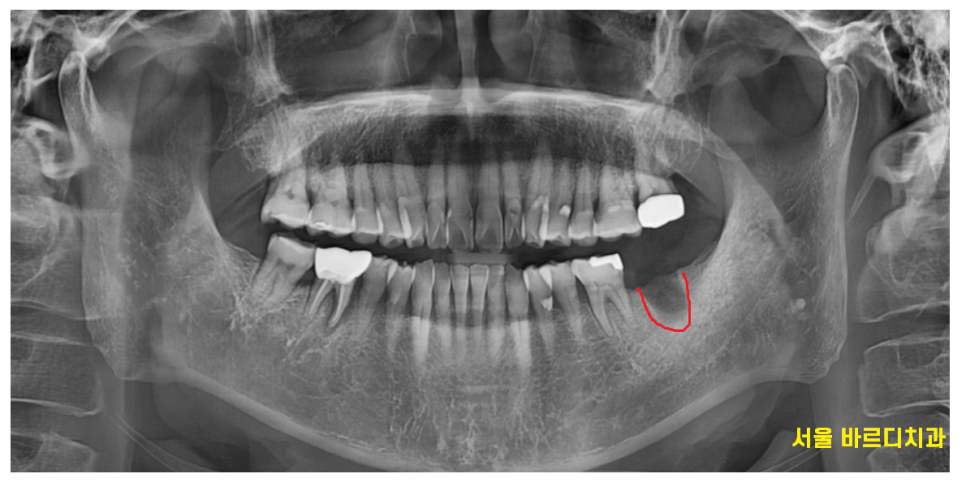

외관상의 문제보다

뿌러지고 방치 되면서

치아 주변 뼈가 녹은게 관찰됩니다.

치료할 부분은 반대편에도 있었는데요

230214

아프지는 않다고 하셨지만

오른쪽 아래 어금니 치아도 염증이 있었습니다.